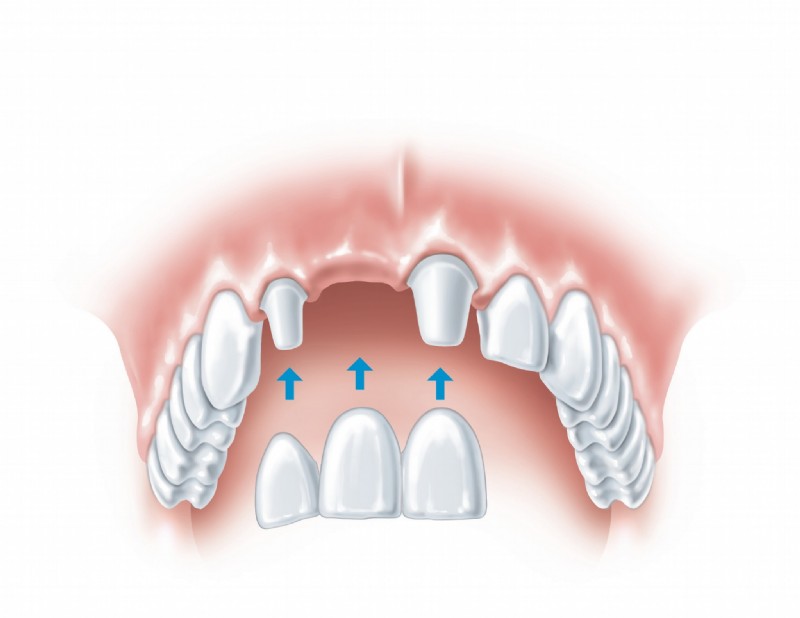

Als Spezialisten auf dem Gebiet der Implantologie wissen wir, wie man hochwertige Implantate stress- und schmerzfrei einsetzt und, wenn erforderlich, zuvor den Knochen aufbaut. Grundlegend werden in einem Beratungsgespräch all Ihre Fragen geklärt. Erst wenn Sie Vertrauen gefasst haben beginnen wir mit der professionellen Behandlung. Wir bieten Ihnen Einzelzahnimplantate, Brücken auf zwei oder mehreren Implantaten, zahnlose Kieferversorgung mit Implantaten, Brücken oder Halteelemente für Prothesen sowie maßgeschneiderte Lösungen für jedes individuelle Problem.

Hochqualitative künstliche Zahnwurzeln können natürliche Zähne sehr effektiv ersetzen. In einem ersten Schritt wird das Implantat-Bett aufbereitet, sodass das Implantat – eine Schraube aus Reintitan – problemlos in den Kiefer geschraubt werden kann. So können einzelne Zähne ersetzt oder Prothesen fixiert werden.